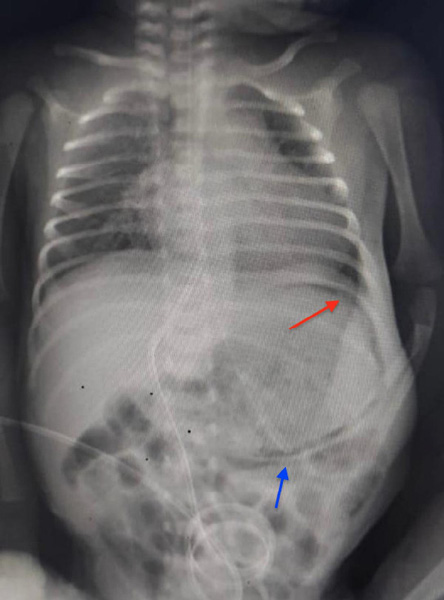

An abdominal radiograph obtained to assess the placement of the umbilical venous catheter revealed a curvilinear lucency, raising clinical suspicion of a serious ailment [Figure 1]. The infant was kept nil per os; parenteral nutrition was started. A repeat X-ray and an ultrasound taken 24 hours after the initial examination suggested that the air collection was resolving. Soon, the aspirates cleared, and oral feeding was initiated. The infant was discharged in good health after two weeks. At a follow-up visit four months after birth, he was thriving and growing well. Informed consent was taken from the patient's mother.

Figure 1: The initial anteroposterior abdominal radiograph of the newborn with an umbilical venous catheter in situ. Curvilinear gastric pneumatosis is seen (red arrow). The gavage tube is abutting the gastric wall (blue arrow).

Gastric pneumatosis is a distinct curvilinear lucency, paralleling and limited to the gastric curvature, which can be observed on a radiograph as shown in Figure 1. Gastric-outlet obstruction, critical illness, widespread necrotizing enterocolitis, sepsis, and asphyxia have been reported as etiologies.1–4 The postulated mechanisms include raised gastric pressure creating a mucosal rent, pneumomediastinum tracking into gastric musculature with positive pressure support application, or infection with gas-producing organisms.5,6 The extraluminal gas accumulation in pneumatosis intestinalis can be submucosal or subserosal. The intramural gas accumulation in the gastric musculature gives a characteristic curvilinear shape to the gastric wall. While pneumatosis intestinalis can involve any part of the large or small intestines, gastric pneumatosis is limited to the gastric area. A differential diagnosis of this condition is emphysematous gastritis, which may present with significant sickness.